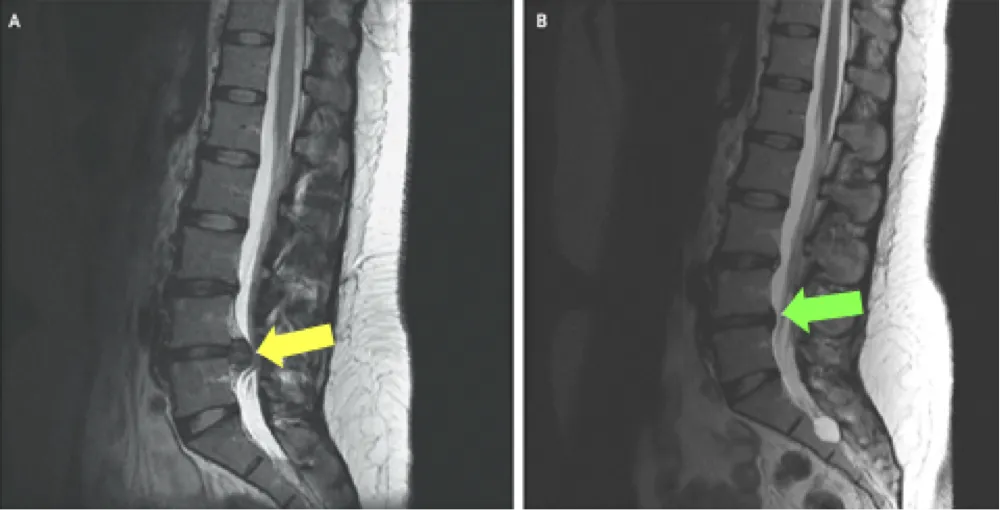

An MRI can reveal a variety of conditions that may be causing sciatica. For example, a herniated disc, which occurs when the soft center of a spinal disc pushes through a crack in the tougher exterior casing, is a common cause of sciatic nerve pain.

An MRI can also show spinal stenosis, a narrowing of the spinal canal that compresses the nerves. Other detectable conditions include spondylolisthesis (slipped disc), degenerative disc disease, and in rare cases, tumors or infections.